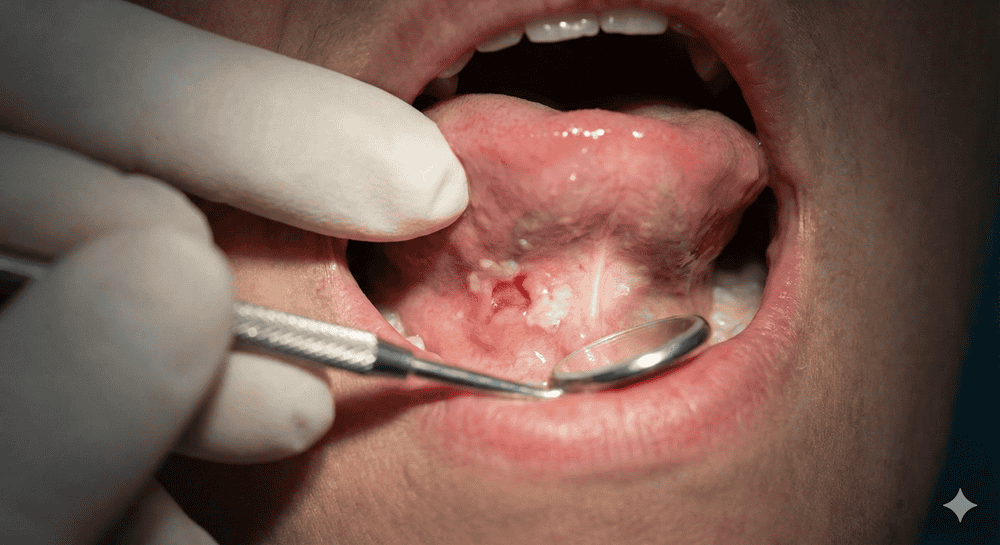

- لکههای قرمز یا سفید در کف دهان یا زیر زبان

- زخم یا توده که بیش از ۲ هفته بهبود نمییابد

- توده یا برجستگی زیر زبان

- ضخیم شدن بافت کف دهان

تشخیص سرطان زیر زبان

تشخیص زودهنگام سرطان زیر زبان میتواند تفاوت بزرگی در موفقیت درمان ایجاد کند. دندانپزشک یا متخصص آسیبشناسی دهان اغلب اولین کسی است که علائم را مشاهده میکند.